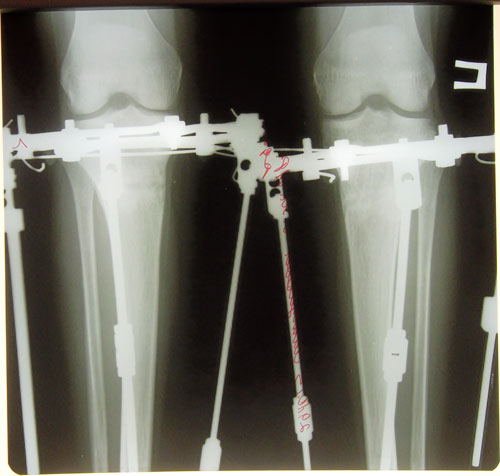

Всем привет.выложили наши фотографии когда я увидела свои ножки мне они не понравились как будто правая иксит а левая прямая.НН сказал что обе идеально ровные по рентгеновскому снимку.но вчера когда присмотрелась еще раз показались не симетричными вобщем настроения нет

Русалка, здравствуйте! Зря вы переживаете! Я как только на фото глянула, сразу в голове мысль - идеально симметричные, пропорциональные, ровные!!! Обе абсолютно одинаковые. Поздравляю вас, желаю скорейшего выздоровления и восстановления!rusalka писал(а):Всем привет.выложили наши фотографии когда я увидела свои ножки мне они не понравились как будто правая иксит а левая прямая.НН сказал что обе идеально ровные по рентгеновскому снимку.но вчера когда присмотрелась еще раз показались не симетричными вобщем настроения нет

Всем доброго вечера.сегодня приходил КН.а вообще он кажды день приходит интересуется как наши успехи.мы говорим ему все о своих болячках.очень тщательно всегда выслушает посмотрит и улыбнется если надо назначит лекарства.сегодня я сказала о своих ногах он еще раз посмотрел и сказал что у меня даже левая иксит о которой я так переживаю т.е у меня легкий икс.ему виднее.ведь он в етой области спец.переживать думаю нечего.ведь НН если говорит что все значит все.все долой хандра и плохое настроение.

Привет, Русалочка. Что за хандра??? Ноги получились СУПЕР!!! Лучше не бывает. Это говорит и НН, это показывает и рентген. Может переживаешь, что НН уехал? Так тебе же легче всего. Живешь недалеко. Приехал, подкрутил и все дела. А если совсем не нравится, можно вернуть исходник. (Шучу). Долой плохое настроение и вперед за новыми изменениями. Я, например, жду снятие и все для того, чтоб пойти и приобрести мини платья, обтягивающие шорты, лосины и все то, что я не могла купить из-за своих кривоножек. Сейчас самое главное - это быстрое сращение костей и образование костной мозоли. Так, что давай живи и радуйся тому что, до исполнения мечты осталось совсем чуть-чуть

Дата операции 19.07.2013г.

Дата снятия аппаратов 30.10.2013г.

Срок лечения 101 день.